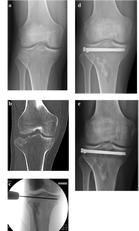

Uno studio, quello firmato da Marco Verona, Giuseppe Marongiu e Antonio Capone - con Gaia Cardoni, Nicola Piras Luca Frigau - plaudito dal board degli esperti quale “esempio di rilevanza clinica”. Uno scenario in cui il gioco di squadra è stato ben sincronizzato. “Lo studio ha evidenziato l'importanza della tecnica mini invasiva in artroscopia nel trattamento delle fratture articolari di ginocchio. La metodica rappresenta una complessa ma efficace tecnica chirurgica che garantisce risultati clinici di elevata qualità con minori tassi di complicanze e più rapida ripresa funzionale rispetto alle tecniche tradizionali” spiega il professor Capone, direttore della Clinica di ortopedia e traumatologia. La ricerca ha per titolo " Arthroscopically assisted reduction and internal fixation (ARIF) versus open reduction and internal fixation (ORIF) for

lateral tibial plateau fractures: a comparative retrospective study", vd Journal of Orthopaedic Surgery and Research (2019) 14:155

Le fratture al piatto tibiale trattate e studiate dall'equipe cagliaritana

“Abbiamo evidenziato il trattamento delle fratture articolari del ginocchio, in particolare del piatto tibiale, con una moderna tecnica mini-invasiva artroscopica e con fissazione percutanea. L’artroscopia consente di visualizzazione attraverso una telecamera ad alta definizione la superficie articolare durante la fase di riduzione della frattura in modo da ripristinare l’anatomia articolare precedente al trauma. A seguire, si posizionano delle viti di stabilizzazione che fissano la frattura e evitano le scomposizioni” rimarca il dottor Verona. “I risultati del nostro studio hanno evidenziato ottimi risultati clinici e un recupero funzionale più rapido, con durata inferiore della necessità d fisioterapia. E soprattutto, un tasso di complicanze post operatorie e di re-intervento inferiore rispetto alle tecniche tradizionali” sottolinea il dottor Marongiu. In breve, una best practice che premia il lavoro degli specialisti della Clinica ortopedica e traumatologica dell’ateneo del capoluogo.